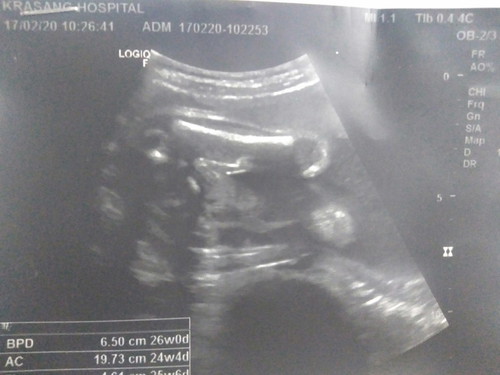

ช่วยดูเพศหน่อยค้า

แม่ๆบ้านไหนดูออกบ้างค่ะว่า ญ.หรือ ช.

ภาพไม่ค่อยชัด ดูยากจังค่ะ